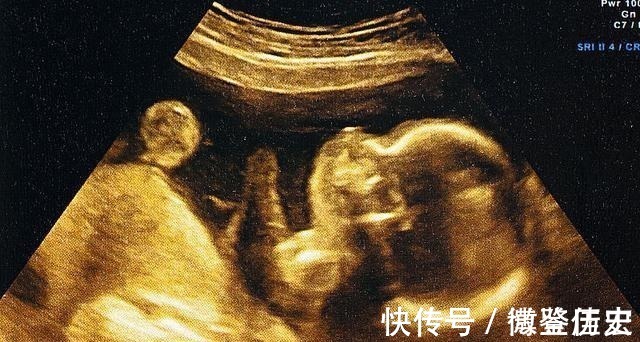

为预防宝宝畸形,我们要注意什么呢?1、重视孕检医院的三维彩超、四维彩超、无创DNA、羊水穿刺等都能帮助我们检查出宝宝是否发育正常。早孕期检查可在10周前或11-14周去做染色体软指标、初步形态学筛查、双胎绒毛膜性判断;中孕期检查可在20-24周做系统性超声筛查;晚孕期检查可在28-34周进行补漏筛查和生长发育检查。